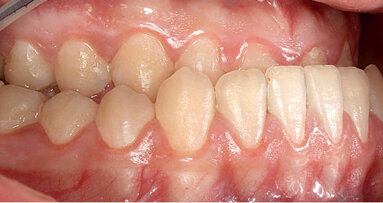

Kazuistika

Pacientka ve věku 38 let přišla do mé ordinace kvůli vyřešení zubních kazů. Při klinickém vyšetření nebyly patrné žádné kazy velkého rozsahu (obr. 1, 2). Až na RTG snímcích typu bitewing (obr. 3, 4), nezbytného prostředku pro diagnostiku v záchovné stomatologii, byly vidět mnohé kariézní léze, které zasahovaly do dentinových tkání. Pacientka požadovala vynikající estetický výsledek, což znamenalo sladění kompozitního materiálu se sklovinnými tkáněmi. Tento požadavek musel být zkombinován s funkční rehabilitací, která by v distálním úseku odolala zatížení žvýkacími silami a zajistila dlouhodobě minimální možné opotřebení. V rámci léčebného plánu bylo pacientce navrženo řešení v podobě přímého ošetření kazů v jednotlivých kvadrantech a nepřímé výplně v zubu 47, které by umožňovalo nejlepší přesnost okrajů a bylo zárukou dlouhodobě vynikajícího výsledku.